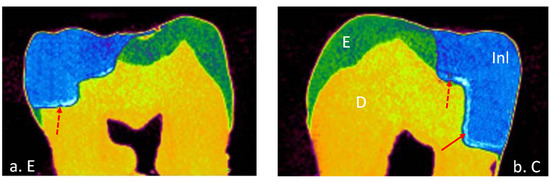

2.7. Micro-Computed Tomoghraphy Scan (Micro-CT) and Image Analyses

2.8. Internal and Marginal Gap Volumes Measurement